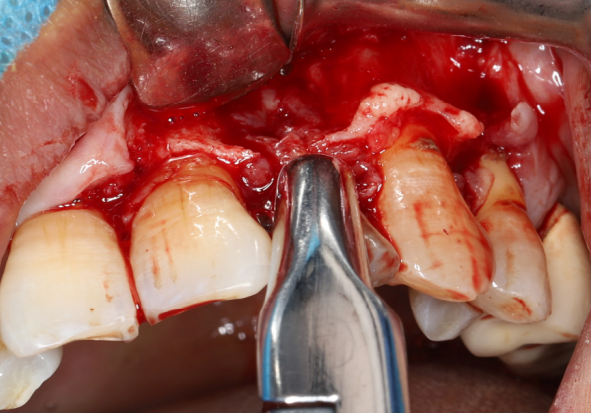

采用不切开骨膜的软组织扩张术——Soft Tissue Extend释放软组织张力

记录翻瓣后原始软组织瓣长度,使用软组织搔刮器(Soft Tissue Extender)冠根向搔刮软组织瓣。

在不切断骨膜的前提下,使用软组织刮治器反复搔刮软组织瓣,可以起到延长软组织瓣的作用。

使用软组织搔刮扩张前后对比:可见在不切断骨膜的前提下,使用软组织搔刮即可获得软组织瓣延长8-9mm。